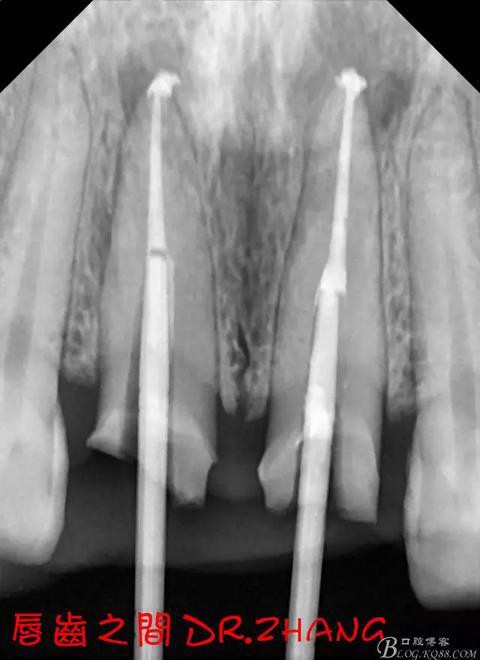

處理:21從修復(fù)體舌側(cè)打開通路 髓腔內(nèi)疑似纖維樁 高速和低速手機聯(lián)合去除樁核 在處理的過程中不斷拍片確認(rèn)方向 去除樁核后拔髓針去除牙膠 只有一個標(biāo)尖 膿液大量滲出 雙氧水和鹽水交替沖洗后 滲出減少 開放髓腔 隔日復(fù)診

復(fù)診:腫脹明顯消失 患者自訴感覺良好 溝通后決定拆除11 21兩顆烤瓷冠后重新修復(fù) 去冠器直接去冠 去除11根管內(nèi)的充填物 15#K銼疏通根管 11 21根長均為16MM平斷面 薩尼S3系統(tǒng)機擴至2S 期間不斷用氯己定和鹽水交替沖洗 吸潮紙尖干燥根管后06 25#試尖

思博安熱牙膠系統(tǒng)根充 燙斷至根尖三分之一處后纖維樁恢復(fù)牙體組織